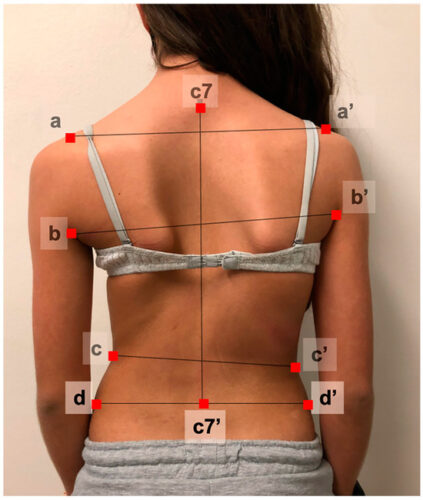

إذا لاحظتِ أن ابنتك لم تمر بعد بمرحلة البلوغ، يُنصح بالقيام بفحص مبكر للعمود الفقري، خصوصًا عند ظهور علامات الانحناء مثل:

ميلان الكتفين أو الوركين

بروز أحد جانبي القفص الصدري

تفاوت طول الأرجل

المتابعة الدورية: فحص العمود الفقري كل 6 أشهر، خصوصًا عند بدء مرحلة البلوغ أو ملاحظة أي تغير في استقامة الظهر.

تسجيل عمر الحيض الأول: يساعد الطبيب على تقدير مرحلة الخطر لتفاقم الانحناء.

الانتباه للنمو السريع: طفرة الطول خلال البلوغ تزيد من احتمالية زيادة زاوية الانحناء، لذا يجب متابعة طول الفتاة بشكل منتظم.